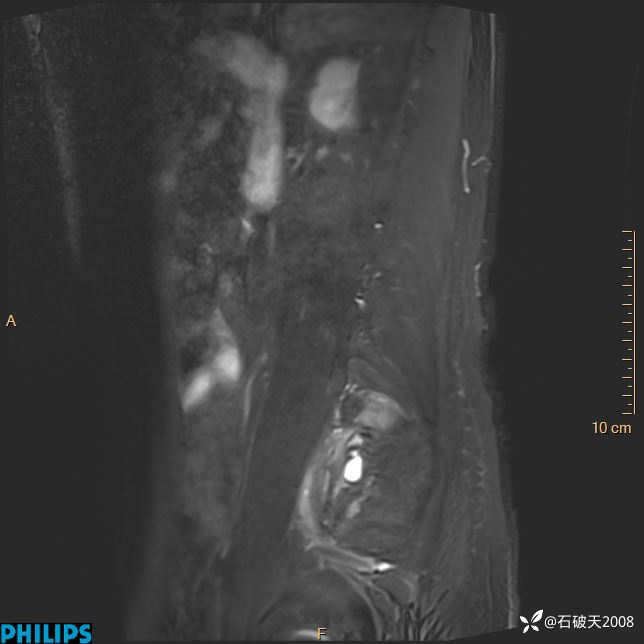

2023年3月份MRI影像

DWI